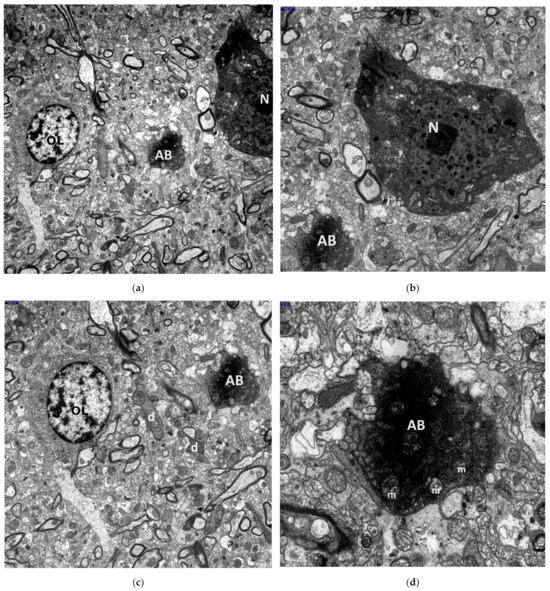

3. Results